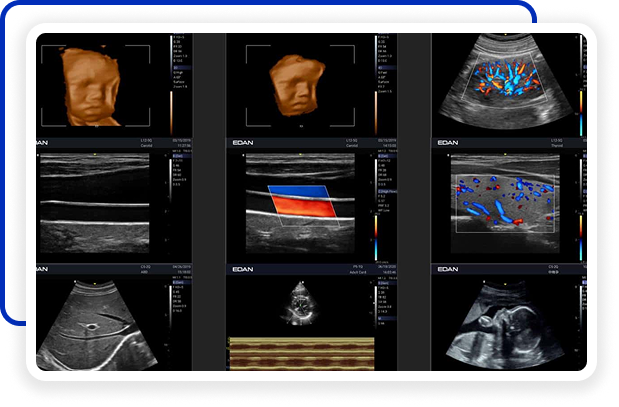

Clareza impressionante

Construído com a inovadora tecnologia Edan TAI e várias tecnologias de processamento de imagem, o Acclarix AX3 pode exibir perfeitamente a imagem de ultrassom em diferentes modos, auxiliando o ultrassonografista a fazer diagnósticos mais precisos.

Galeria de Imagens